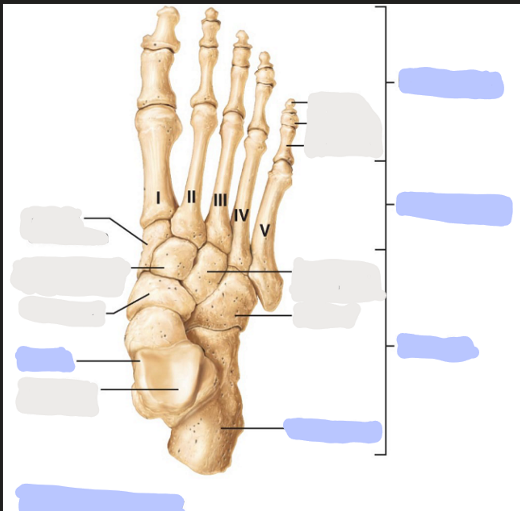

What is this picture of?

Superior view of the right foot

What is here?

Where are the Phalanges?

What is here?

Where are the Metatarsals?

What is here?

Where are the Tarsals?

What is here?

Where is the Calcaneus?

What is here?

Where is the Talus?

How many planar Phalanges are there?

14

How many Metatarsals are there?

5

How many Tarsals are there?

7